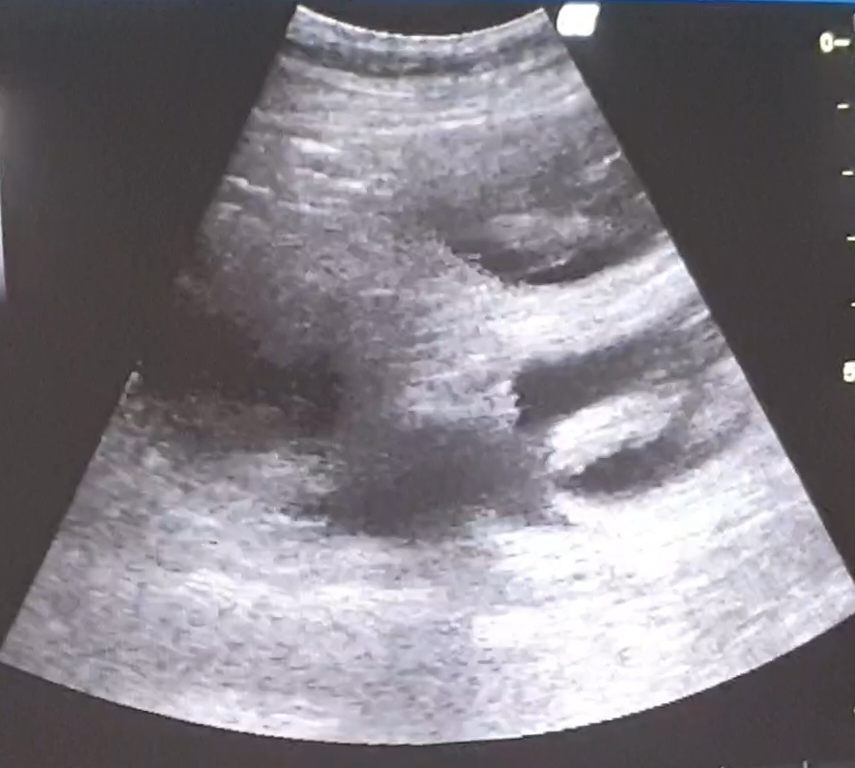

Tag 36 – Unsere Mama und ihre Babys… 😍😊😍 Hier ein paar Infos: Aus den Embryos sind nun Föten geworden. Die Ausbildung der Organe ist abgeschlossen und die Babys sehen nun auch schon aus, wie kleine Hunde. Jetzt könnte man sogar feststellen, wer ein Junge oder ein Mädchen ist. Die Herzen schlagen schon etwa seit Tag 25 und sind nun auch mit einem Stetoskop hörbar. Die Fellfarbe entwickelt sich gerade und damit auch die individuelle Zeichnung jedes Welpchens. Die kleinen Hundebabys sind inzwischen fester Bestandteil in unserer Familie. Sie werden morgens mit begrüßt und abends wünschen wir ihnen eine gute Nacht. Zwischendurch werden sie von uns geknuddelt, was Mama auch sehr genießt. 🥰😂🥰